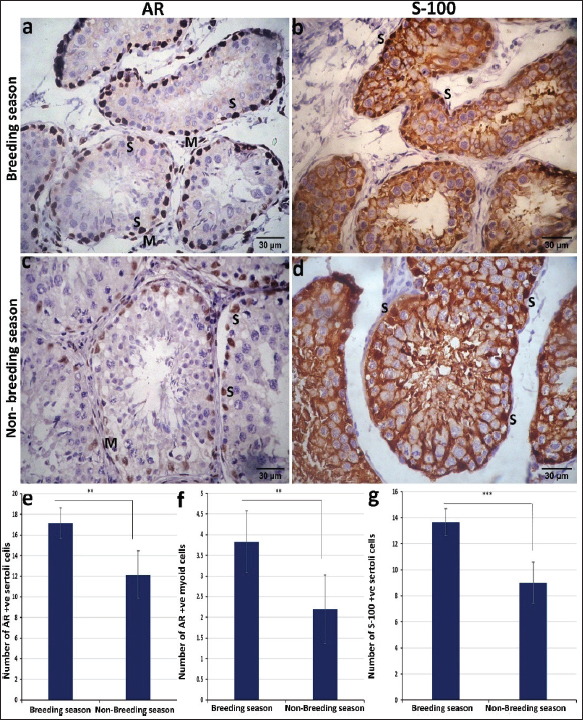

Immunohistochemical studies showed that the androgen receptor antibody was expressed at the seminiferous tubules, particularly in the sertoli and myoid cells. The reaction was obviously strong in sertoli and myoid cells in the breeding season, in contrast to the non-breeding season, where the intensity of the reaction was intermediate in sertoli cells and very mild to negative in myoid cells (Fig. 3a and c). Statistically, the number of AR-positive Sertoli cells and myoid cells was higher in the breeding season than in the non-breeding season p < 0.05 (Fig. 3e and f). The immunoreaction for S-100 protein revealed strong S-100 expression in Sertoli cells, especially in their nuclei, which appeared darker in the breeding season than in the non-breeding season (Fig. 3b and d). Histomorphometry revealed a highly significant difference (p < 0.001) in the number of S-100-positive Sertoli cells between the breeding and non-breeding seasons (Fig. 3g).

Fig. 3. Photomicrograph of the immunohistochemical expression of ram testis during the breeding season (a and b) and the non-breeding season (c and d). The intensity of the reaction for the AR of the sertoli and myoid cells was strong in the breeding season (a), intermediate in the sertoli cells, and very mild to negative in the myoid cells in the non-breeding season (c). Immunoreactivity for S-100 protein revealed stronger expression in the breeding season (b) than in the non-breeding season (d). Morphometric analysis for the number of AR-positive sertoli cells/tubule area (e), number of AR-positive myoid cells/tubule area (f), and number of S100 protein-positive cells per seminiferous tubule (g). Data are presented as mean ± SE. ** significant different p < 0.05, *** highly significant p < 0.001. DiscussionSignificant seasonal differences were observed between the breeding and nonbreeding periods. This difference was considerably higher. Rosa and Bryant (2003) confirmed that sheep breeds found in mid- and high-altitude areas generally reveled seasonality in their reproduction ability, which is proven by a few studies that effect on reproductive traits of rams (Zamiri et al., 2010). The testicular measurements that were taken in our study manifested a clear seasonal variation. Measurements of the tests, including length, width, and circumference, showed a marked increase during the breeding season relative to the non-breeding periods. This variance reverberates that the tests show physiological activation under the effect of high testosterone concentrations and increased gonadotropic release during the reproductive season. There was a higher significant difference (p > 0.05) for all measures (length, width, and circumference), which agrees with the result reported by Belkhiri et al. (2017). This conclusion may be related to the increase in testicular volume, which is directly related to the increase in the diameter of the seminiferous tubules and the improvement of spermatogenesis activity. Several previous studies in rams and bucks have reported the same findings, indicating that testicular dimensions are true indicators of reproductive capacity (Zaher et al., 2020). According to our findings, hormonal levels significantly varied by season. There was a higher significant difference (p > 0.05) in testosterone, LH, and FSH levels. These findings concur with those of Abecia et al. (2012), who found that season reproductivity is a phenomenon primarily impacted by changes during the year and the photoperiod, leading to clearly defined reproductive variation. In agreement with Elbaz and Abdel Razek (2019), who observed variation in the hormonal profile in various sheep breeds over the different seasons of the year. The present study investigated the ultrasonographic images and seasonal variations of the accessory sex glands, epididymis, and testes in rams, with a focus on the mediastinum testis, seminal vesicles, and disseminating part of the prostate during breeding and non-breeding seasons. Our findings revealed a significant increase in the size of the mediastinum testis and higher echogenicity of the parenchyma during the breeding season compared with the nonbreeding season. This matched the findings of Elbaz and Abdel Razek (2019). These changes are dedicated to increasing testicular activity and improving spermatogenesis, which are strongly influenced by seasonal fluctuations in testosterone secretion. Previous studies in rams (Kaulfuss et al., 2006) and other small ruminants have also reported enlargement of the testes and increased echogenicity of the mediastinum testis during the peak of reproductive activity, supporting the present result. The seminal vesicles had a clear lobulated appearance in addition to hyperechoic septa that separated the glandular tissue, which became more prominent during the breeding season. This finding is attributed to the oversecretion of seminal plasma under the effect of androgens. Comparable features have been reported in bulls and stallions, where the glandular tissue becomes more hyperechogenic and highly lobulated during periods of higher sexual activity (Edwards, 2008; Gnemmi and Lefebvre, 2009). Therefore, the marked lobulation observed in rams may act as an ultrasonographic indicator of reproductive status. Taken together, these seasonal changes highlight the strong relationship between ultrasonographic findings and ram endocrine activity. The observed increase in testicular size and increased echogenicity of the testes and accessory sex glands during the breeding season are consistent with elevated testosterone levels and improved reproductive performance. The distinct lobulation of the seminal gland and the seasonal enhancement of the accessory gland and mediastinum are important indicators of reproductive activity and may serve as practical markers for breeding soundness evaluation. The primary function of the testes is sperm production, with the seminiferous tubules, Sertoli cells, and Leydig cells being key components. In addition, a network of ducts and other testicular tissues plays a supportive role in the production and transport of sperm (Elzoghby et al., 2014, Al-Mahmodi, 2018). Our work revealed that the seminiferous tubules were tubular, round, or oval in shape with a mean diameter from 166.74 ± 6.536 (breeding season) to 151.53 ± 4.46 (nonbreeding season). This is in contrast to the findings of Al-Mahmodi (2018) who reported that the mean diameters of the seminiferous tubules were 264 ± 2.9 µm in rams and 245 ± 1.9 µm in bucks. Seminiferous tubules were lined with stratified epithelium consisting of different stages of one row spermatogenic cells, large primary and smaller secondary spermatocytes, and round spermatids clustered at the lumen of the tubules (Tala’a and Hamdi, 2023). This result is in line with our findings. Within the seminiferous tubules, Sertoli cells are positioned at the basal layer and display oval to pyramidal morphology, containing ovoid-shaped nuclei. These cells are relatively few and serve as supporting cells at the basement membrane of the seminiferous tubules. Although they do not directly produce sperm or testosterone, Sertoli cells perform several critical functions that facilitate spermatogenesis and spermatozoa transport (Al-Mahmodi, 2018). The testes’ interstitial connective tissue comprises blood vessels, fibroblasts, loose connective tissue cells, and interstitial Leydig cells. Leydig cells are nearly absent before the onset of puberty, when testosterone production begins. Their primary role is the synthesis and secretion of androgens, particularly testosterone, the principal male sex hormone (Sikarwar et al., 2022). Our work revealed that immunohistochemical studies showed that the androgen receptor antibody was expressed at the seminiferous tubules, especially in Sertoli cells and myoid cells, which appeared obviously in the breeding season compared to the non-breeding season. (Rodríguez et al. (2008) reported that Sertoli cells and contractile peritubular cells express a high percentage of the androgen receptor, whereas the germinal line is negative in reaction. Our study showed that the immunoreaction for S-100 protein revealed strong S-100 expression in Sertoli cells, especially in their nuclei, which appeared darker in the breeding season. The intensity of S-100 protein immunoreactivity in Sertoli cells is influenced by cyclic changes within the seminiferous epithelium. Relatively strong immunoreactivity is observed during spermatid elongation stages. Notably, this study highlights the particularly intense staining observed in the intratesticular excurrent duct system (Amselgruber et al., 1994) . S-100 immunoreactivity was pronounced in Sertoli cells, with the protein localized within both the cytoplasmic and nuclear compartments (Abd-Elmaksoud et al., 2014). Moreover, S-100 expression was absent in germ cells, leydig, and myofibroblast cells of the studied species at different stages. Spermatogonia, spermatocytes in different phases of meiosis, spermatids, and spermatozoa were consistently negative for S-100 protein. A strong immunoreaction for S-100 in leydig cells was characteristic for the testes of rats and cats, and a weak immunoreaction of this cell type was also observed in horses and pigs. Staining of particular cells has been found in rodents and carnivores (Amselgruber et al., 1994). ConclusionThe abovementioned study concluded that differences were evident in the hormonal profile, ultrasonographic findings, and histopathological characteristics of the tests, and this was associated with increased testicular activity and more active seminiferous tubules histologically in the breeding season compared to the non-breeding seasons. These results confirm the strong seasonal influence on reproductive performance in rams. AcknowledgmentsNone. Conflict of interestThe authors have no conflicts of interest to declare. FundingNot applicable. Authors’ contributionsAll authors contributed equally to this study. Data availabilityAll data were included in this manuscript. ReferencesTala'a, A.A. and Hamdi, Y. 2023. Histomorphometric study of seminiferous tubules and epididymis in adult ram. Univ. Thi-Qar J. Agri. Res. 12, 206–217. Abd-Elmaksoud, A., Shoeib, M.B. and Marei, H.E.S. 2014. Localization of S-100 proteins in the testis and epididymis of poultry and rabbits. Anatomy Cell. Biol. 47, 180–187. Abecia, J.A., Forcada, F. and González-Bulnes, A. 2012. Hormonal control of reproduction in small ruminants. Anim. Reprod. Sci. 130, 173–179. Aboul-Ela, M.B., Aboul-Naga, A.M., Shalaby, T.H. and Maijala, K. 1987. Physiological response to climatic changes in Finnish Landrace ewes imported to Egypt and their half-sibs raised in Finland. Livestock. Prod. Sci. 17, 179–185. Aboul-Naga, A.M., Aboul-Ela, M.B. and Hassan, F. 1992. Manipulation of reproductive activity in subtropical sheep. Small. Ruminant. Res. 7, 151–160. Ahmadi, B., Lau, C.P.S., Giffin, J., Santos, N., Hahnel, A., Raeside, J., Christie, H. and Bartlewski, P. 2012. Suitability of epididymal and testicular ultrasonography and computerized image analysis for assessment of current and future semen quality in the ram. Exp. Biol. Med. 237, 186–193. Ahmed, N. and Noakes, D. 1995. Seasonal variation in testes size, libido and plasma testosterone concentration in British goat. Anim. Sci. 61, 553–559. Ahmed, A. 2008. Biological evaluation of Barki sheep under two different breeding seasons. Egypt. J. Anim. Prod. 45, 15–24. Al-Mahmodi, A. 2018. Microscopical and biometrical investigations of the testes in adult ram and adult buck in Al-Najaf Al-Ashraf Province. Amselgruber, W.M., Sinowatz, F. and Erhard, M. 1994. Differential distribution of immunoreactive S-100 protein in mammalian testis. Histochemistry 102, 241–245. Andrade, A.K.G., Soares, A.T., Freitas, F.F., Silva, S., Peña-Alfaro, C.E., Batista, A. and Guerra, M. 2014. Testicular and epididymal ultrasonography in Santa Inês lambs raised in Brazil. Anim. Reprod. 11, 110–118. Belkhiri, Y., Bouzebda-Afri, F., Bouzebda, Z. and Djaout, A. 2017. Testicular morphometric measurements of Ouled Djellal lambs from birth to puberty. Global Veterinaria 18, 85–91. Camela, E.S.C., Nociti, R.P., Santos, V.J.C., Macente, B.I., Maciel, G.S., Feliciano, M.A.R., Vicente, W.R.R., Gill, I., Bartlewski, P.M. and Oliveira, M.E.F. 2017. Ultrasonographic characteristics of accessory sex glands and spectral Doppler indices of the internal iliac arteries in peri- and post-pubertal Dorper rams raised in a subtropical climate. Anim. Reprod. Sci. 184, 29–35. Chandolia, R.K., Bartlewski, P.M., Omeke, B.C., Beard, A.P., Rawlings, N.C. and Pierson, R.A. 1997. Ultrasonography of the developing reproductive tract in ram lambs: effects of a GnRH agonist. Theriogenology 48, 99–117. Edwards, J.F. 2008. Pathologic conditions of the stallion reproductive tract. Anim. Reprod. Sci. 107, 197–207. Elbaz, H.T. and Abdel Razek, E.M. 2019. Ultrasonographic measurements of reproductive organs of male goat during non-breeding season. PSM. Vet. Res. 4, 13–23. Elzoghby, E., Sosa, G. and Hussein, M. 2014. Postnatal development of the sheep testis. Benha. Vet. Med. J. 26, 186–190. Fthenakis, G., Gouletsou, P., Mavrogianni, V. and Fragkou, I. 2010. Sheep diagnostic medicine. Small Ruminant Res. 92(1), 1. Gnemmi, G. and Lefebvre, R.C. 2009. Ultrasound imaging of the bull reproductive tract: an important field of expertise for veterinarians. Vet. Clin. North Am. Food Anim. Pract. 25, 767–779. Gouletsou, P.G. 2017. Ultrasonographic examination of the scrotal contents in rams. Small. Ruminant. Res. 152, 100–106. Gouletsou, P.G. and Fthenakis, G.C. 2010. Clinical evaluation of reproductive ability of rams. Small. Ruminant. Res. 92, 45–51. Gouletsou, P.G., Amiridis, G.S., Cripps, P.J., Lainas, T., Deligiannis, K., Saratsis, P. and Fthenakis, G.C. 2003. Ultrasonographic appearance of clinically healthy testicles and epididymides of rams. Theriogenology 59, 1959–1972. Hulet, C.V., Shupe, W.L., Ross, T. and Richards, W. 1986. Effects of nutritional environment and ram effect on breeding season in range sheep. Theriogenology 25, 317–323. Islam, A.B.M.M. and Land, R.B. 1977. Seasonal variation in testis diameter and sperm output of rams of breeds of different prolificacy. Anim. Sci. 25, 311–317. Karagiannidis, A., Varsakeli, S. and Karatzas, G. 2000. Characteristics and seasonal variations in semen of Alpine, Saanen and Damascus goat bucks born and raised in Greece. Theriogenology 53, 1285–1293. Kaulfuss, K.H., Giucci, E., Süss, R. and Wójtowski, J. 2006. An ultrasonographic method to study reproductive seasonality in ewes isolated from rams. Reprod. Domest. Anim. 41, 416–422. Kunavongkrit, A., Suriyasomboon, A., Lundeheim, N., Heard, T.W. and Einarsson, S. 2005. Management and sperm production of boars under differing environmental conditions. Theriogenology 63, 657–667. Moore, B.W. 1965. A soluble protein characteristic of the nervous system. Biochem. Biophysical Res. Commun. 19, 739–744. Perez, C.R., Lopez, A., Castrillejo, A., Bielli, A., Laborde, D., Gastei, T., Tagle, R., Queirolo, D., Franco, J., Forsberg, M. and Rodriguez-Martinez, H. 1997. Reproductive seasonality of Corriedale rams under extensive rearing conditions. Acta. Vet. Scand. 38, 109–117. Ribeiro , M.D.S., Quirino, C.R., Bartholazzi Junior, A. and Pacheco, A. 2017. Biometry and ultrasound evaluation of testicles and accessory glands in Santa Ines rams. Revista Brasileira De Zootecnia 46, 317–323. Rodríguez, H., Espinoza, O., Sarabia, L., Tamayo, C., Sepúlveda, M., Inostroza Escobar, J., Araya, J. and Moriguchi, K. 2008. Histological and functional organization in human testicle: expression of receptors c-kit and androgens. Rosa, H.J.D. and Bryant, M.J. 2003. Seasonality of reproduction in sheep. Small. Ruminant. Res. 48, 155–171. Sanad, N.H., Abbas, H.R., Yaseen, A.A., Habeeb, I.A. and Alsalim, H.A. 2021. Hormonal, histological and comparative study of the effect of pure ginseng on testicular function in the breeding/non-breeding season of rams in Basrah. Arch. Razi. Inst. 76, 1519–1535. Sargison , N., Crilly, J. and Hopker, A. 2018. Practical Lambing and Lamb Care: a Veterinary GuideOX4 2DQ, UK: Oxford. Sikarwar, V.S., Mašláni, A., Hl., na, M., Fathi, J., Mates, T., Pohořelý, M., Meers, E., Šyc, M. and Jeremiáš, M. 2022. Thermal plasma-assisted pyrolysis and gasification of RDF by utilizing sequestered CO2 as gasifying agent. J. CO2. Utilization. 66, 102275. Suvarna, K.S., Layton, C. and Bancroft, J.D. 2018. Bancroft’s Theory and Practice of Histological Techniques. Amesterdam, Holand: Elsevier. Swelum, A.A., Ayadi, M., Alhidary, I., Alowaimer, A. and Abouheif, M. 2017. Relationships between body fatness, leptin, testosterone and reproductive performance in ram lambs as affected by level and frequency of feeding. Theriogenology 89, 79–85. Todini, L., Malfatti, A., Terzano, G.M., Borghese, A., Pizzillo, M. and Debenedetti, A. 2007. Seasonality of plasma testosterone in males of four Mediterranean goat breeds and in three different climatic conditions. Theriogenology 67, 627–631. Zaher, H., Alawaash, S. and Swelum, A. 2020. Effects of season and breed on reproductive performance of sheep. J. Anim. Reprod. Biotechnol. 35, 149–154. Zamiri, M.J., Khalili, B., Jafaroghli, M. and Farshad, A. 2010. Seasonal variation in seminal parameters, testicular size and plasma testosterone concentration in Iranian Moghani rams. Small Ruminant Res. 94, 132–136. Zarei, M.A., Farshad, A. and Akhondzade, S. 2009. Variations in thyroidal activity during estrous cycle and natural breeding season in Markhoz goat breeds. Pak. J. Biol. Sci. 12, 1420–1424. Zimmer, D.B., Cornwall, E.H., Landar, A. and Song, W. 1995. The S100 protein family: history, function and expression. Brain Res. Bull. 37, 417–429. | ||